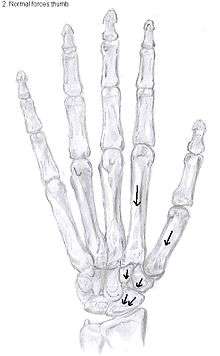

Trapeziectomy

The most simple form out of the four variations is the trapeziectomy alone, also referred as the simple trapeziectomy.[34] During this procedure, the trapezium bone is removed without any further surgical adjustments.

The trapezium bone will be removed through an approximately three centimeter long incision along the lateral side of the thumb. To preserve surrounding structures, the trapezium bone will be removed through fragmentation of the bone (the bone will therefore be broken into pieces).

An empty gap is left by the trapeziectomy and the wound is closed with sutures. Despite this gap, no significant changes in function of the thumb are reported.[33] After the surgery, the thumb will be immobilized with a cast.

Trapeziectomy with TI

Some physicians still believe that it is better to fill the gap left by the trapeziectomy. They assume that filling the gap with a part of a tendon is preferable in terms of function, stability and position of the thumb. They are afraid that leaving a gap might result in complications such as shortening or subluxation of the thumb.

During trapeziectomy with TI, a tendon interposition is performed.[36] A longitudinal strip of the palmaris longus tendon is separated. If this tendon is absent (which is the case in 13% of the population), half of the flexor carpi radialis tendon (FCR) can be used.

The tendon is then formed into a circular shape and placed in the gap, where it will be stabilized by sutures.[14]